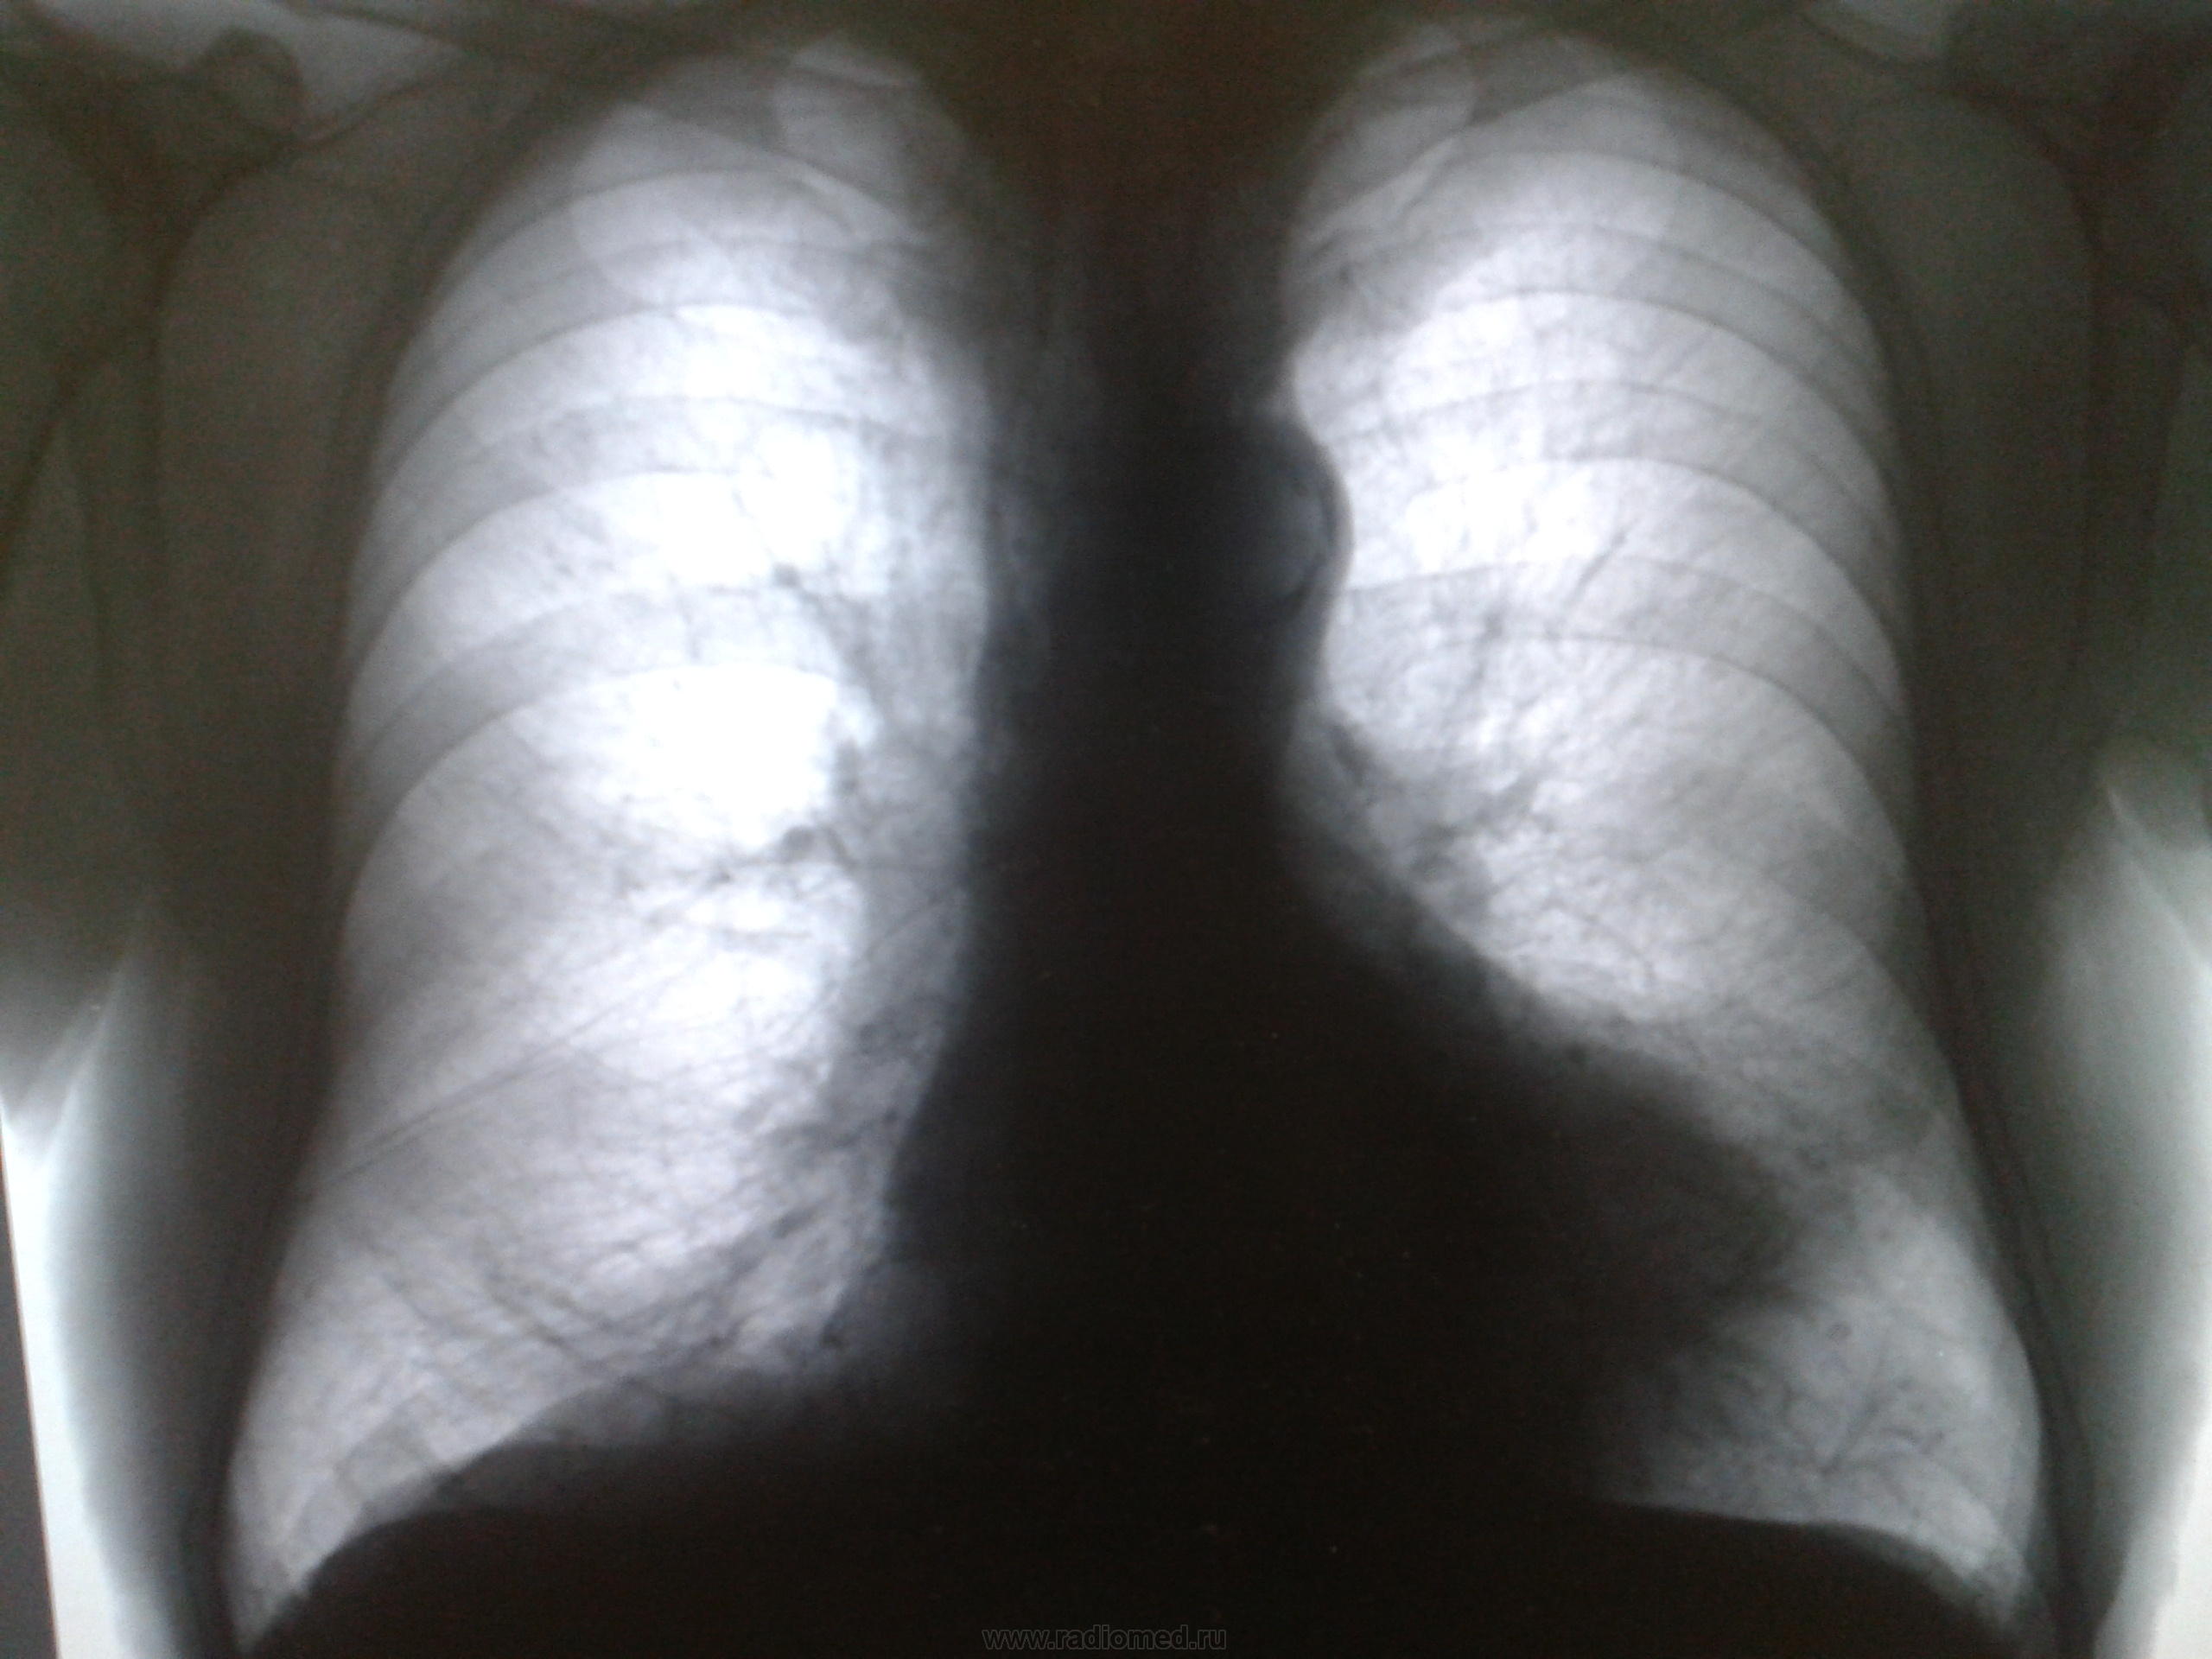

Больной Х 68 лет,находится в хирургическом отделении по поводу спаечной кишечной непроходимости. 14.01.14 назначили ФЛГ. Вот результаты. Помогите чем можете . Мне непонравилась тень над сердцем слева(мои мысли ,что это или тимома или киста вилочковой железы). В анамнезе ХОБЛ.Особых жалоб со стороны органов дыхания не предъявляет!!

На боковом не видно, проецируется на тень сердца, может быть киста перикарда

Тимома - это обоазование переднего средостения, на снимках переднее средостение свободно, какая тимома?

Розовая линия-граница сердца, над ней синим???

Где та тень, и где тимус... Вот к перикарду запросто может иметь отношение. И на боковом её видно.

Эта тень в язычковых сегментах. Может быть что угодно, в смысле - нельзя исключить рак.

Для тимомы и кист вилочковой железы более характерно расположение в верхнем и среднем этажах средостения , для этих заболеваний характерна миостения. Можно думать о кисте перикарда, дермоидной кисте, осумкованном парамедиастинальном плеврите. В таких непонятных случаях стараюсь найти рентгенархив.

Аневризма левого желудочка

Возможно,сердце так выглядит из-за деформации грудной клетки,-на "грудь сапожника"похоже,-ведь у больного ХОБЛ и давно.

+1 к вдавлению грудины - "груди сапожника". Это меняет скиалогию сердца.

Всё же прямой снимок недостаточно качественный для того, что бы на нем уверенно можно было определить контур дуги левого желудочка. Думаю, что автору следует обратить внимание на некачественную работу лаборанта и дать задание переделать снимок. Хорошо бы также посмотреть интересующую область на скопии.

Да, скопия здесь не помешает. В дифряд ещё можно поставить ателектаз язычковых сегментов.Кажется, что средостение немного "уехало" влево.

Да. Нужно исключать рачек. Скопия была бы кстати.